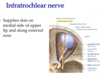

What are the long ciliary nerves? What nerve do they originate from?

What is their function?